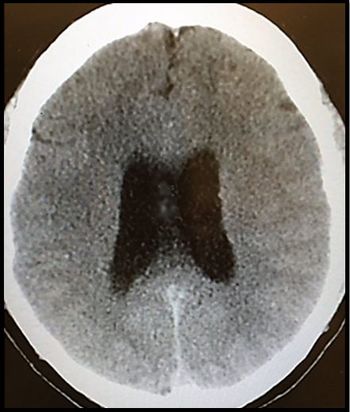

A 62-year-old man is transported to the ED after becoming incontinent in the middle of the night. He has a history of HCV. What do test results suggest?

A 34-year-old man with a history of HIV says family members are exaggerating his symptoms but that the headache and double vision are bothersome.